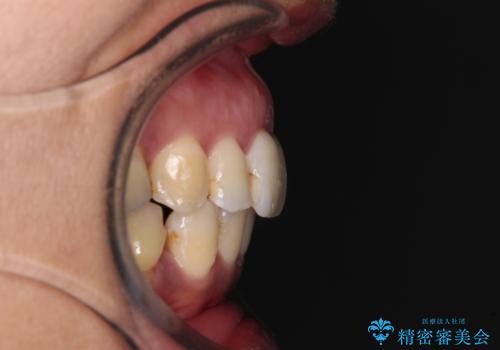

- 歯列全体が内側に倒れ込んでいることと、口元の突出感を気にして来院された患者様です。

上下ともに歯列が狭窄しており、前方に突出している状態でした。

歯が重なるような叢生も認められたため、上下左右の第一小臼歯4本を抜歯して、口元が引っ込むように治療を行うこととしました。

口元を引っ込めることができたため、口を閉じるときに力が入っていて皺のよっていた顎先も、スムーズに閉じられるようになったことで力がかからなくなりました。